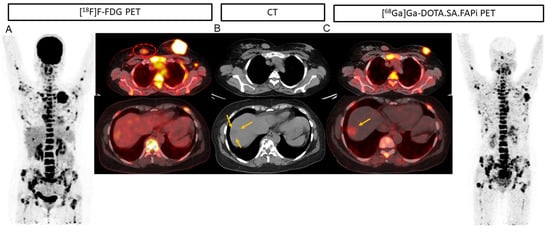

2. Results

2.3. Lesion-Based Analysis

2.4. Comparison of Uptake and TBRs in Tumor Lesions